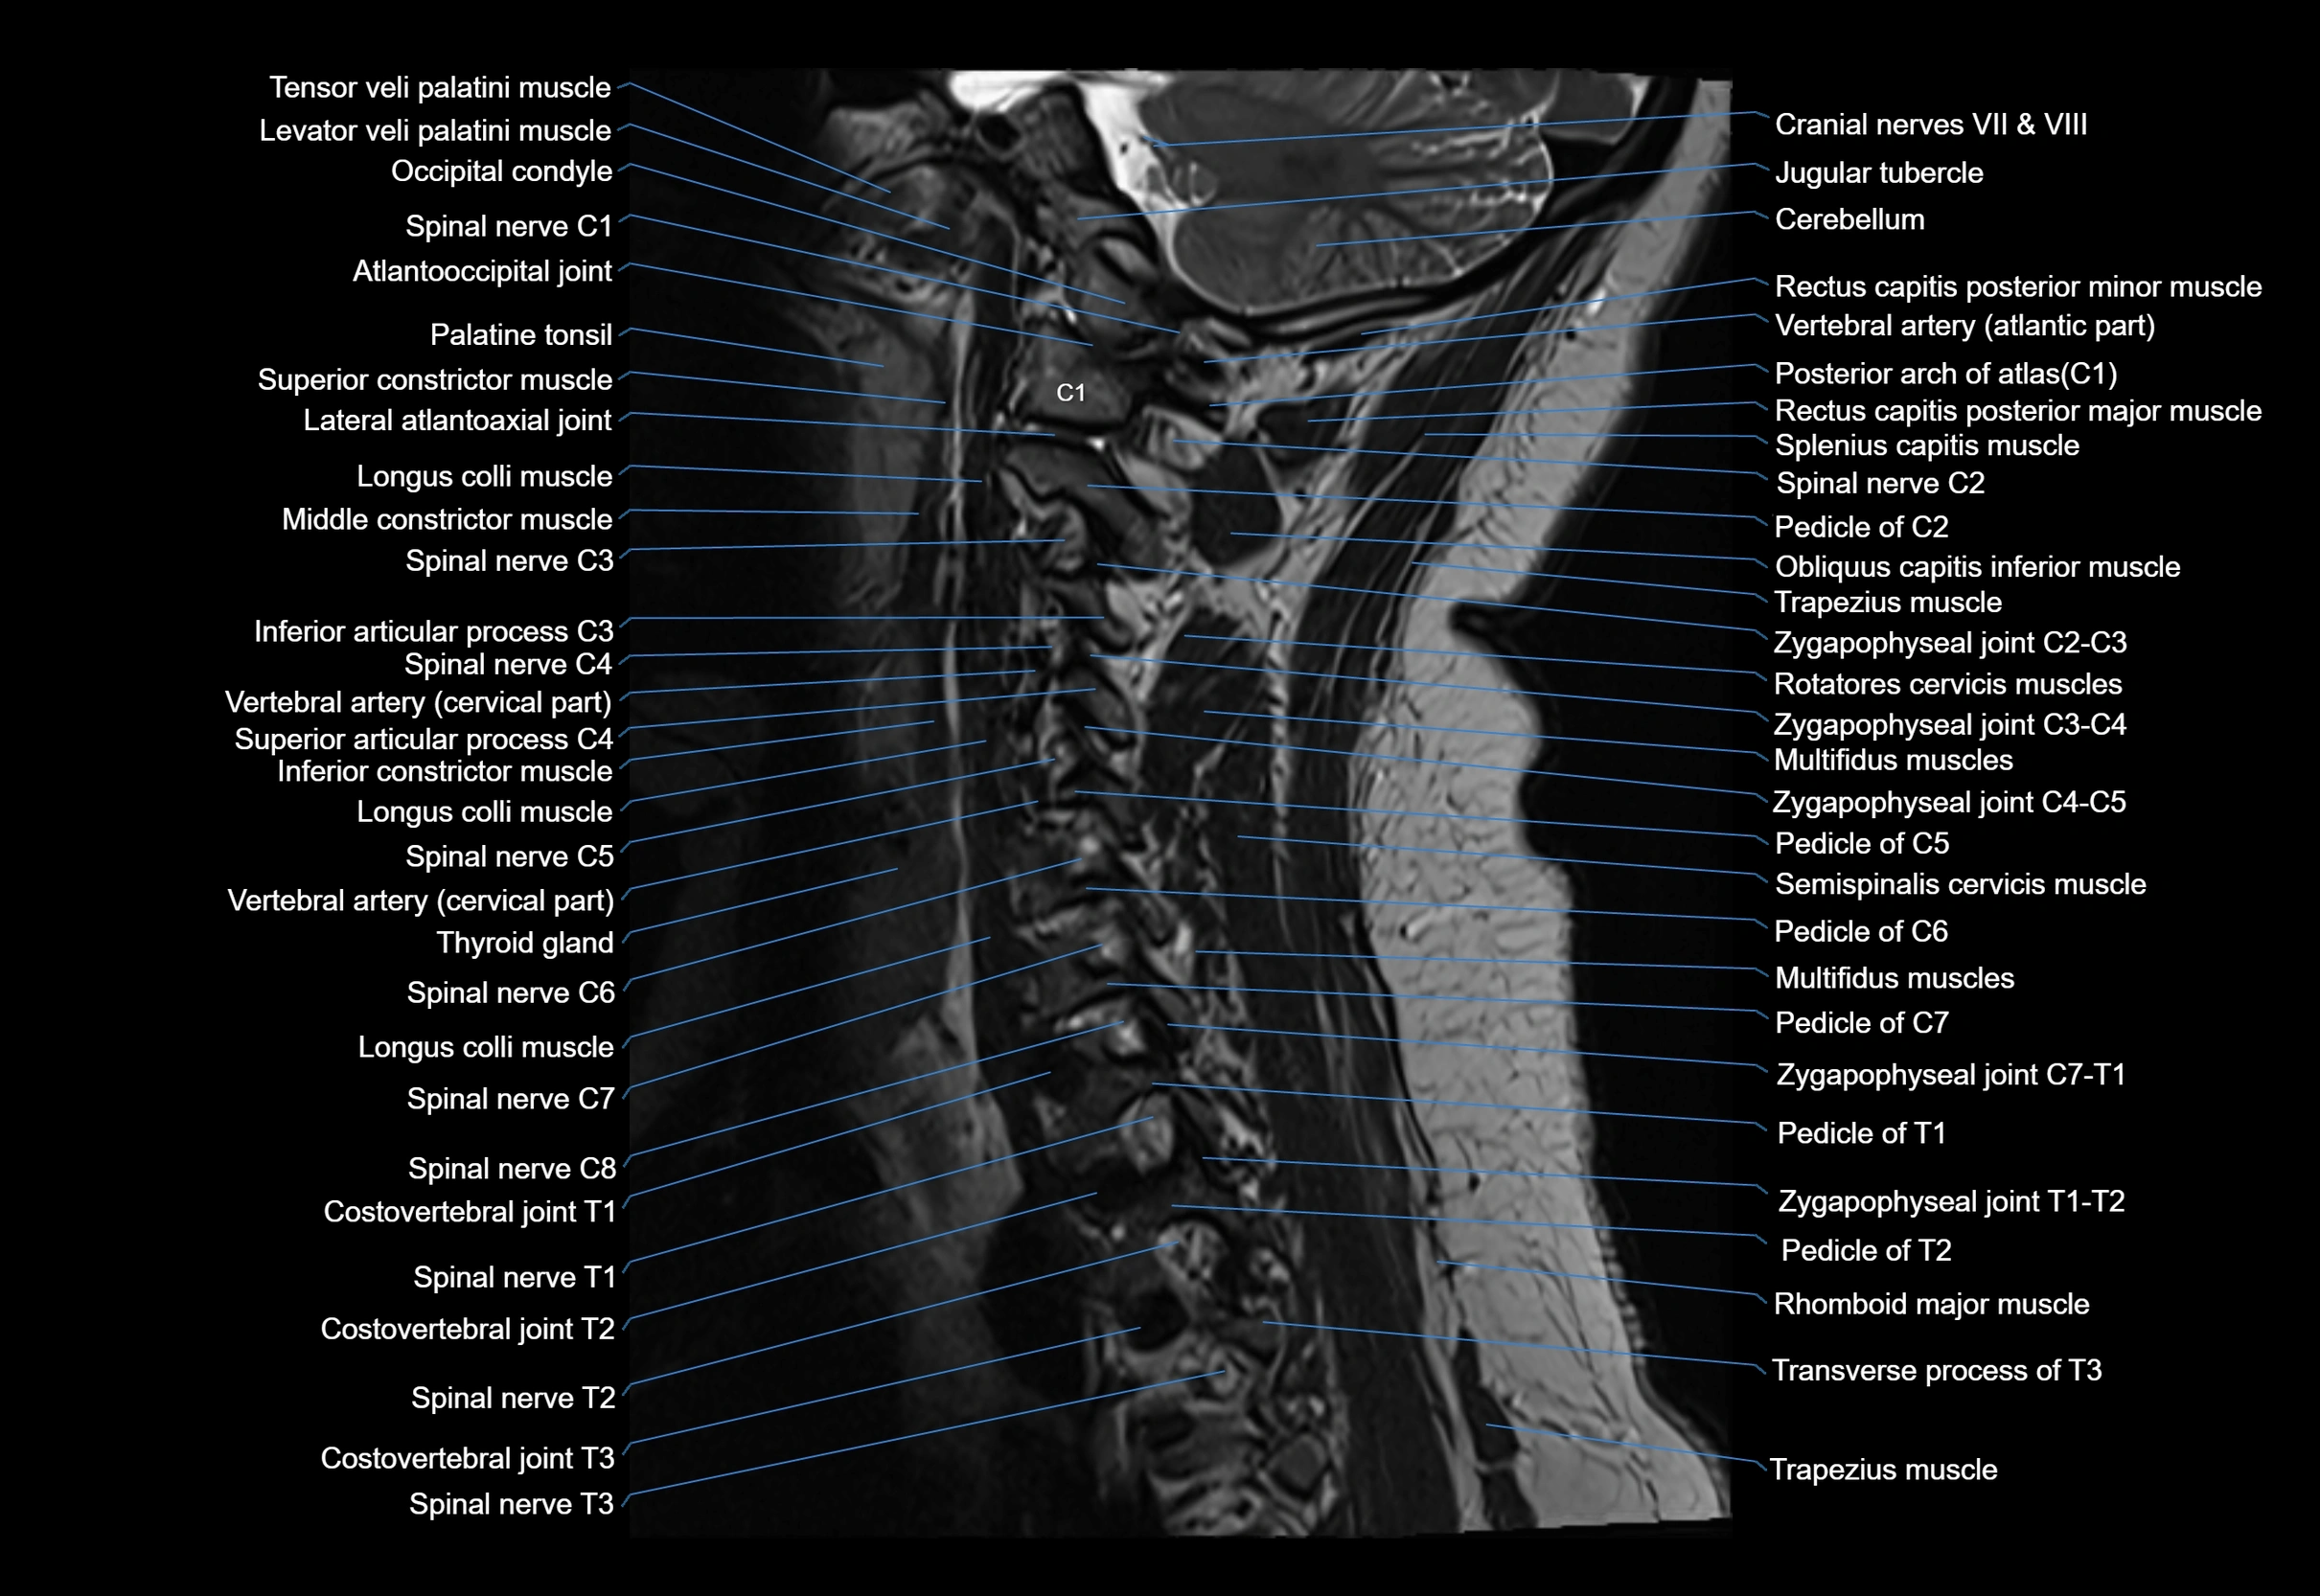

MRI appearance

T1-weighted images:

• Annular epiphysis: Low signal cortical rim at the vertebral margin

• Adjacent marrow: Intermediate-to-high signal in the vertebral body

• Disc interface: Clear delineation between bone and annulus

T2-weighted images:

• Annular epiphysis: Low signal intensity line

• Endplate cartilage (in younger patients): Intermediate signal

• Intervertebral disc: High signal nucleus pulposus

STIR:

• Annular epiphysis: Low signal cortical rim

• Adjacent marrow: Suppressed fat signal with preserved bony outline

• Utility: Highlights marrow and endplate interface in developing spine

MRI image

image